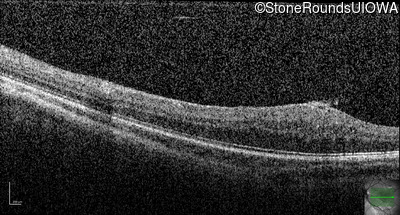

Infrared Fundus Photograph - Right - 20/2000

Exemplar